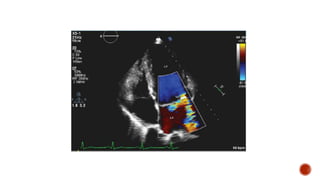

 DOPPLER ASSESSMENT: COLOUR DOPPLER

 Color flow Doppler

 In current practice, it is common to judge a small jet occupying less than 20

percent of the left atrial area as mild, a middle-sized jet as moderate, and a large

jet (more than 40 percent and extending into the pulmonary veins) as severe